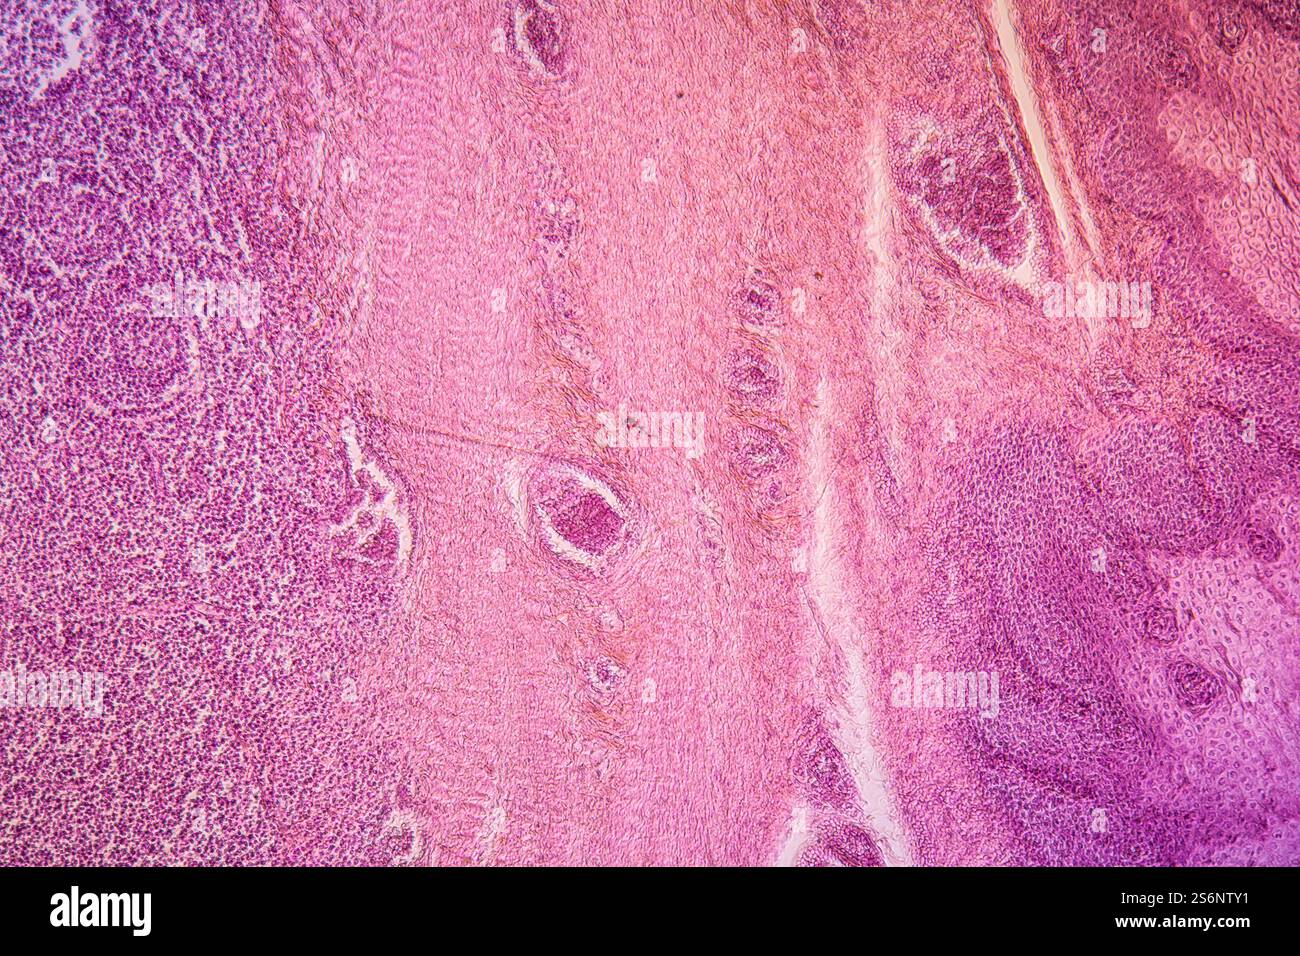

Tonsillen erkranktes Gewebe 100x Stockfotohttps://www.alamy.de/image-license-details/?v=1https://www.alamy.de/tonsillen-erkranktes-gewebe-100x-image640952117.html

Tonsillen erkranktes Gewebe 100x Stockfotohttps://www.alamy.de/image-license-details/?v=1https://www.alamy.de/tonsillen-erkranktes-gewebe-100x-image640952117.htmlRF2S6NTY1–Tonsillen erkranktes Gewebe 100x

Tonsillen erkranktes Gewebe 100x Stockfotohttps://www.alamy.de/image-license-details/?v=1https://www.alamy.de/tonsillen-erkranktes-gewebe-100x-image648168925.html

Tonsillen erkranktes Gewebe 100x Stockfotohttps://www.alamy.de/image-license-details/?v=1https://www.alamy.de/tonsillen-erkranktes-gewebe-100x-image648168925.htmlRF2SJEJ25–Tonsillen erkranktes Gewebe 100x

Mandelentzündung krankes Gewebe 100x Stockfotohttps://www.alamy.de/image-license-details/?v=1https://www.alamy.de/mandelentzundung-krankes-gewebe-100x-image274329575.html

Mandelentzündung krankes Gewebe 100x Stockfotohttps://www.alamy.de/image-license-details/?v=1https://www.alamy.de/mandelentzundung-krankes-gewebe-100x-image274329575.htmlRMWX8P4R–Mandelentzündung krankes Gewebe 100x

Mandelentzündung krankes Gewebe 100x Stockfotohttps://www.alamy.de/image-license-details/?v=1https://www.alamy.de/mandelentzundung-krankes-gewebe-100x-image274329690.html

Mandelentzündung krankes Gewebe 100x Stockfotohttps://www.alamy.de/image-license-details/?v=1https://www.alamy.de/mandelentzundung-krankes-gewebe-100x-image274329690.htmlRMWX8P8X–Mandelentzündung krankes Gewebe 100x

Mandelentzündung krankes Gewebe 100x Stockfotohttps://www.alamy.de/image-license-details/?v=1https://www.alamy.de/mandelentzundung-krankes-gewebe-100x-image227729286.html

Mandelentzündung krankes Gewebe 100x Stockfotohttps://www.alamy.de/image-license-details/?v=1https://www.alamy.de/mandelentzundung-krankes-gewebe-100x-image227729286.htmlRFR6DY0P–Mandelentzündung krankes Gewebe 100x

Mandelentzündung krankes Gewebe 100x Stockfotohttps://www.alamy.de/image-license-details/?v=1https://www.alamy.de/mandelentzundung-krankes-gewebe-100x-image227729294.html

Mandelentzündung krankes Gewebe 100x Stockfotohttps://www.alamy.de/image-license-details/?v=1https://www.alamy.de/mandelentzundung-krankes-gewebe-100x-image227729294.htmlRFR6DY12–Mandelentzündung krankes Gewebe 100x

Mandelentzündung krankes Gewebe 100x Stockfotohttps://www.alamy.de/image-license-details/?v=1https://www.alamy.de/mandelentzundung-krankes-gewebe-100x-image274329638.html

Mandelentzündung krankes Gewebe 100x Stockfotohttps://www.alamy.de/image-license-details/?v=1https://www.alamy.de/mandelentzundung-krankes-gewebe-100x-image274329638.htmlRMWX8P72–Mandelentzündung krankes Gewebe 100x

Mandelentzündung krankes Gewebe unter dem Mikroskop 100x Stockfotohttps://www.alamy.de/image-license-details/?v=1https://www.alamy.de/mandelentzundung-krankes-gewebe-unter-dem-mikroskop-100x-image274312924.html

Mandelentzündung krankes Gewebe unter dem Mikroskop 100x Stockfotohttps://www.alamy.de/image-license-details/?v=1https://www.alamy.de/mandelentzundung-krankes-gewebe-unter-dem-mikroskop-100x-image274312924.htmlRMWX80X4–Mandelentzündung krankes Gewebe unter dem Mikroskop 100x

Mandelentzündung krankes Gewebe 100x Stockfotohttps://www.alamy.de/image-license-details/?v=1https://www.alamy.de/mandelentzundung-krankes-gewebe-100x-image227729281.html

Mandelentzündung krankes Gewebe 100x Stockfotohttps://www.alamy.de/image-license-details/?v=1https://www.alamy.de/mandelentzundung-krankes-gewebe-100x-image227729281.htmlRFR6DY0H–Mandelentzündung krankes Gewebe 100x

Mandelentzündung krankes Gewebe unter dem Mikroskop 100x Stockfotohttps://www.alamy.de/image-license-details/?v=1https://www.alamy.de/mandelentzundung-krankes-gewebe-unter-dem-mikroskop-100x-image274312906.html

Mandelentzündung krankes Gewebe unter dem Mikroskop 100x Stockfotohttps://www.alamy.de/image-license-details/?v=1https://www.alamy.de/mandelentzundung-krankes-gewebe-unter-dem-mikroskop-100x-image274312906.htmlRMWX80WE–Mandelentzündung krankes Gewebe unter dem Mikroskop 100x